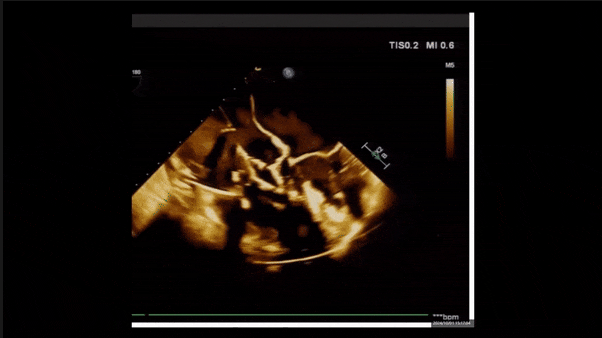

術(shù)后即刻返流

術(shù)后即刻返流三維

術(shù)后三維超聲

術(shù)后即刻經(jīng)食道超聲可見,三尖瓣假體瓣膜位置合適,牛心包瓣葉運(yùn)動狀態(tài)良好,開閉正常,瓣周及瓣葉對合緣處未見明顯返流,心電圖及心包狀態(tài)較術(shù)前無明顯變化。

術(shù)前術(shù)后返流情況對比